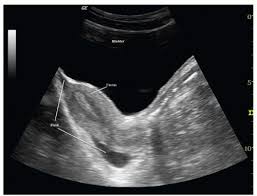

You might be wondering about that “trace of fluid” your doctor mentioned during a pelvic exam. Don’t worry, it’s usually nothing to be alarmed about! Physiological pelvic intraperitoneal fluid simply means there’s a small amount of free fluid in your pelvis, specifically in the pouch of Douglas.

Think of it like this: your body naturally produces a bit of fluid to lubricate and protect the internal organs. This fluid can sometimes collect in the pouch of Douglas, which is the lowest point in your pelvic cavity.

Free fluid in the Pouch of Douglas is a common finding during medical imaging. This simply means that there is a small amount of fluid in the space between your uterus and rectum. In most cases, free fluid in the Pouch of Douglas is harmless and doesn’t require any treatment. It can be caused by a number of things, including:

Normal menstrual cycles: A little bit of fluid is normal during your period.

Ovulation: Fluid can also accumulate in this area during ovulation.